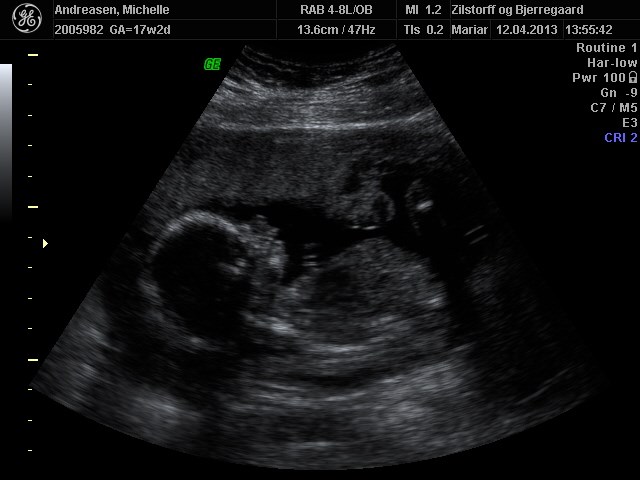

Her er nogle billeder af vores pige 17+2

Vedhæftede fotos (klik for at se i fuld størrelse)